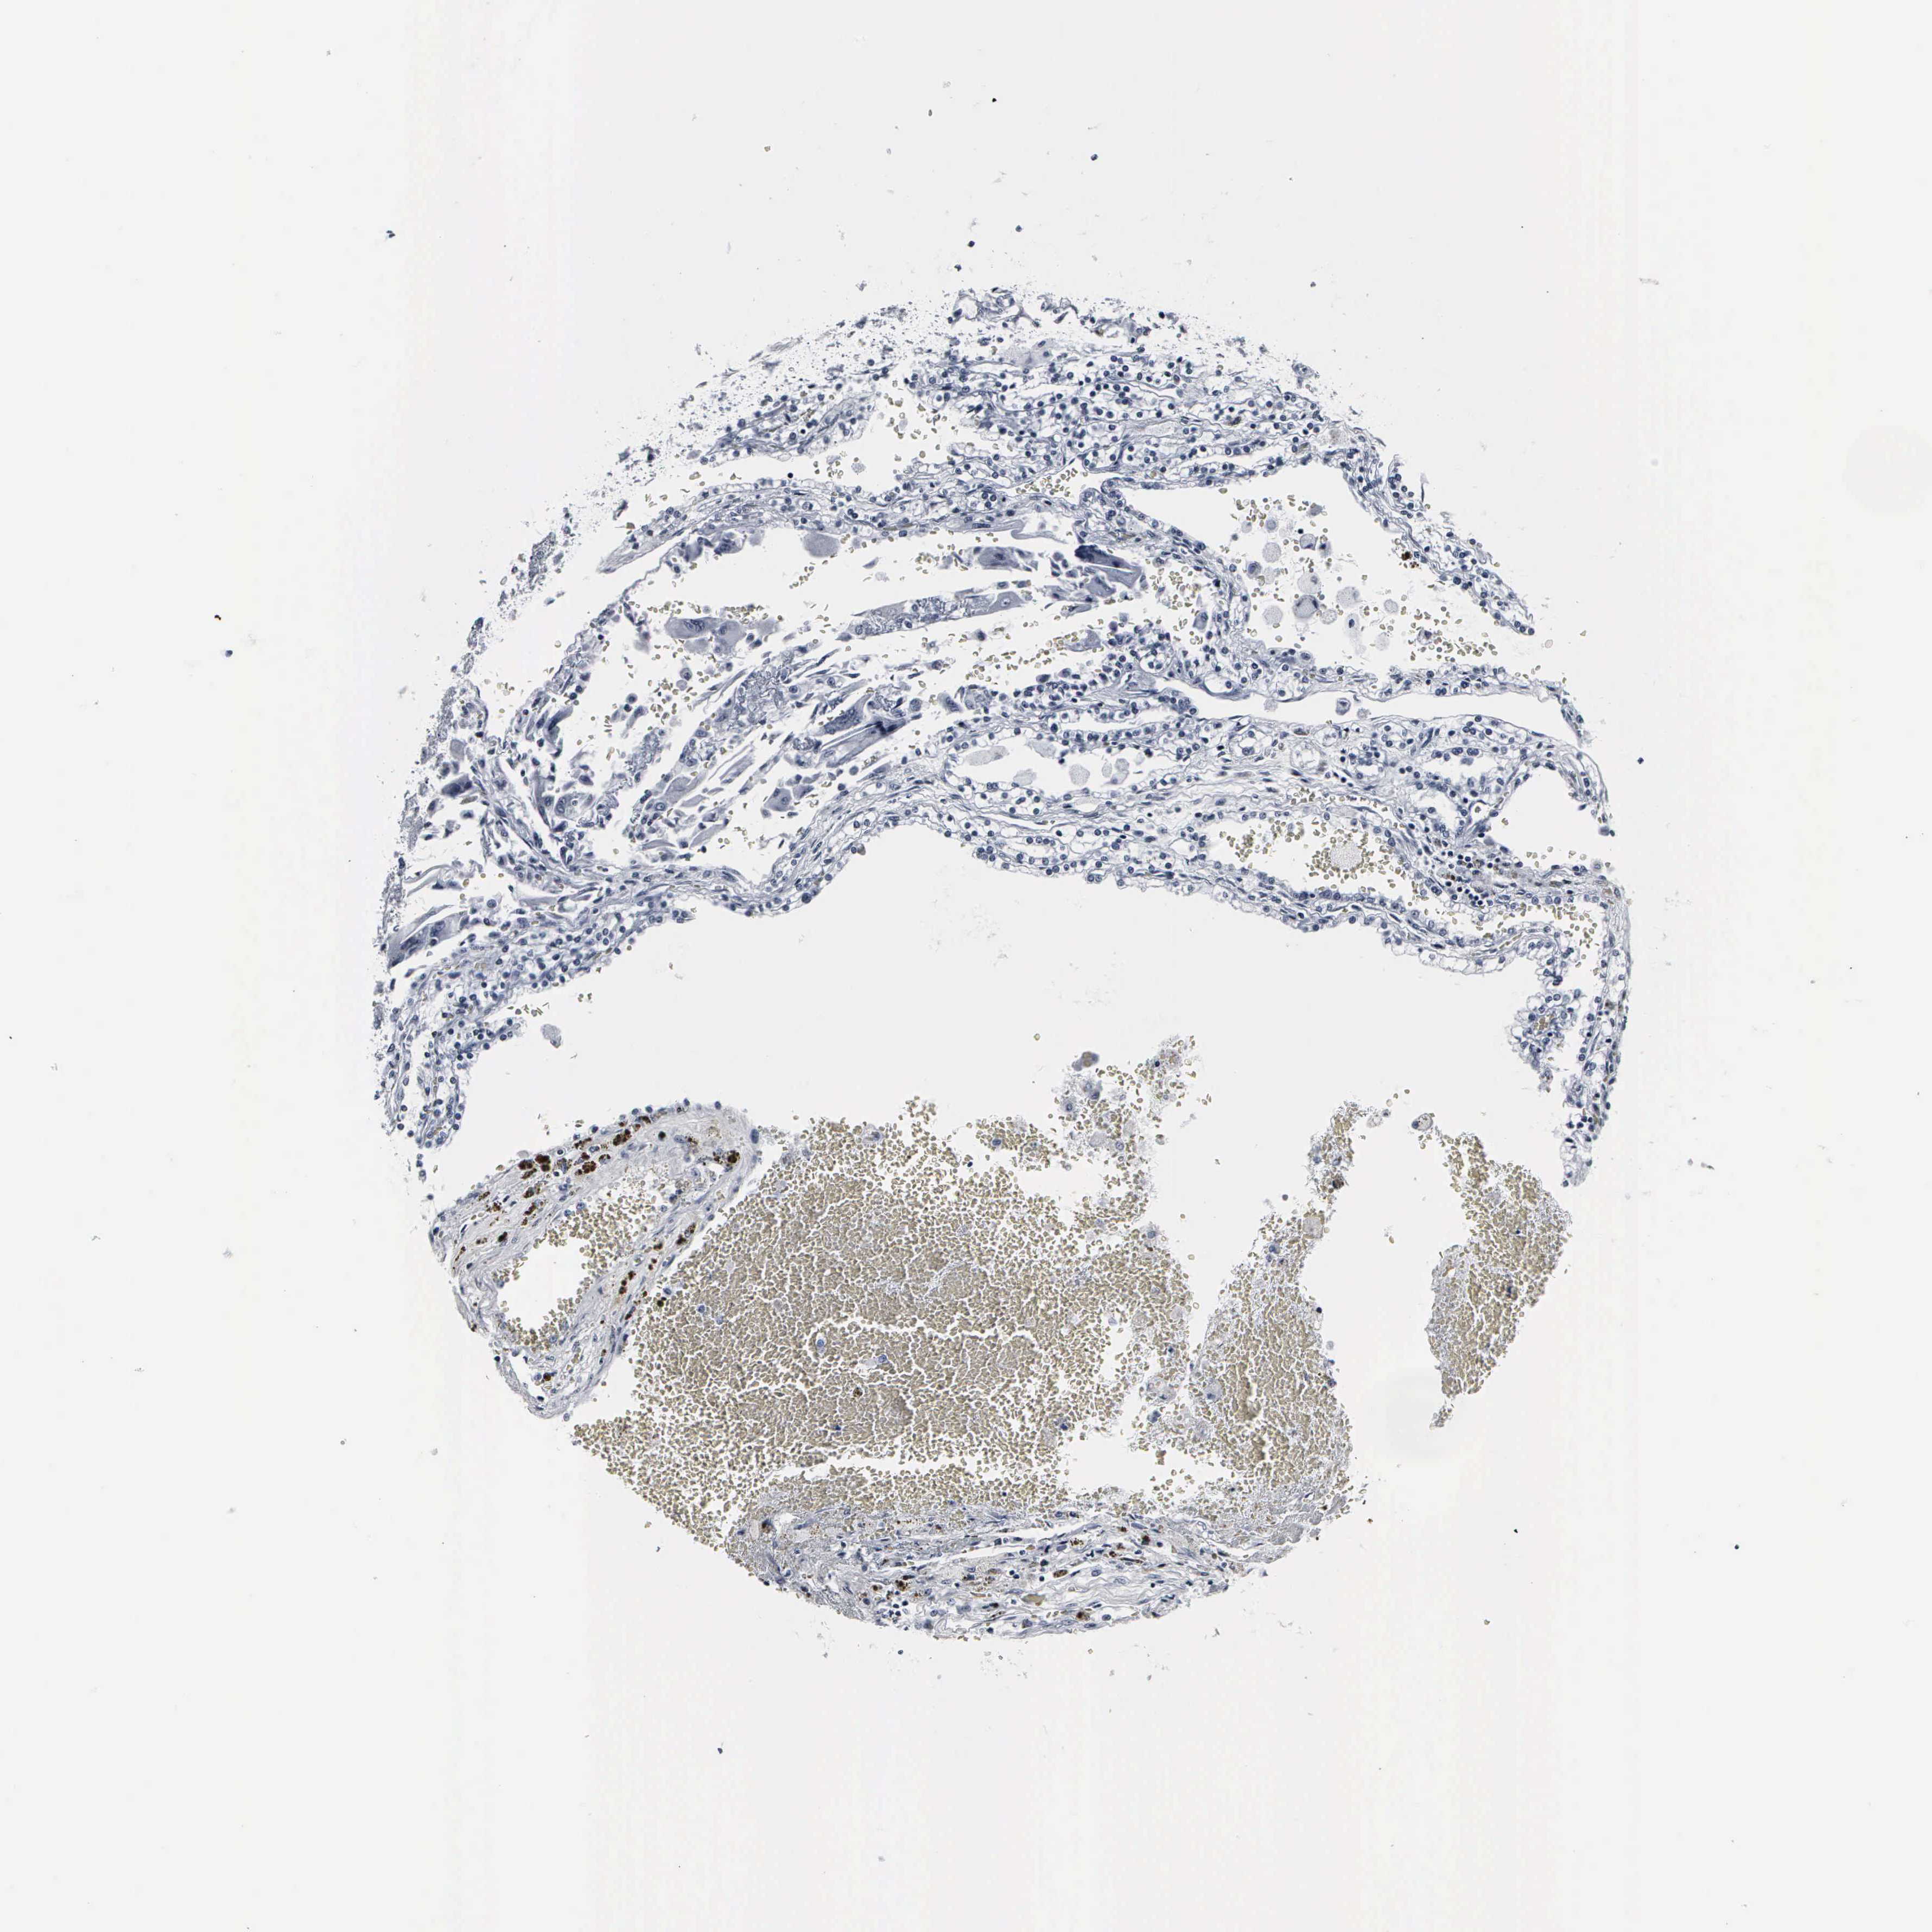

KIDNEY RENAL PAPILLARY CELL CARCINOMA (TCGA) - Interactive survival scatter ploti

The Survival Scatter plot shows the clinical status (i.e. dead or alive) for all individuals in the patient cohort, based on the same data that underlies the corresponding Kaplan-Meier plots. Patients that are alive at last time for follow-up are shown in blue and patients who have died during the study are shown in red.

The x-axis shows the expression levels (FPKM) of the investigated gene in the tumor tissue at the time of diagnosis. The y-axis shows the follow-up time after diagnosis (years). Both axes are complimented with kernel density curves demonstrating the data density over the axes. The top density plot shows the expression levels (FPKM) distribution among dead (red) and alive patients (blue). The right density plot shows the data density of the survived years of dead patients with high and low expression levels respectively, stratified using the cutoff indicated by the vertical dashed line through the Survival Scatter plot. This cutoff is automatically defined based on the FPKM cutoff that minimizes the p-score. The cutoff can be changed by dragging the vertical line or by entering a cutoff value in the square labeled "Current cut-off".

Under the Survival Scatter plot the p-score landscape (black curve; left axis) is shown together with dead median separation (red curve; right axis). Dead median separation is the difference in median mRNA expression between patients who have died with high and low expression, respectively. It is calculated as follows: median FPKM expression of dead patients with high expression - median FPKM expression of dead patients with low expression. This is intended to aid the user in visually exploring custom cutoffs and the associated p-scores and dead median separation.

Individual patient data is displayed and can be filtered by clicking on one or more of the category buttons on the top of the page. Categories describing expression level and patient information include: high, low, alive, dead, female, male and tumor stages. The scale of the x-axis can be toggled between linear and log-scale by clicking on the "x log" button. Mouse-over function shows TCGA ID, patient information and mRNA expression (FPKM) for each patient.

& Survival analysisi

Kaplan-Meier plots summarize results from analysis of correlation between mRNA expression level and patient survival. Patients were divided based on level of expression into one of the two groups "low" (under cut off) or "high" (over cut off). X-axis shows time for survival (years) and y-axis shows the probability of survival, where 1.0 corresponds to 100 percent.

DGCR2 is not prognostic in Kidney Renal Papillary Cell Carcinoma (TCGA)